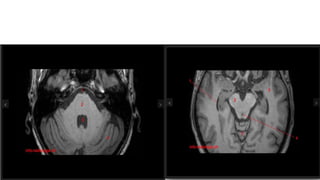

CNS RADIOLOGY FOR RADIATION ONCOLOGISTS